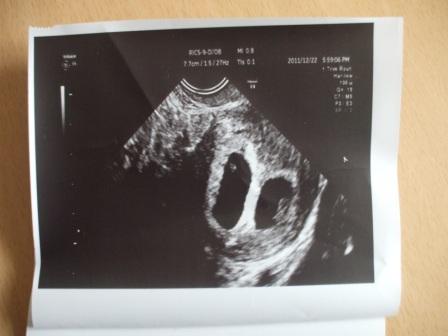

Jó ötlet a táblázat nagyon! Édik a kis maszatkáid az uh-s képen!